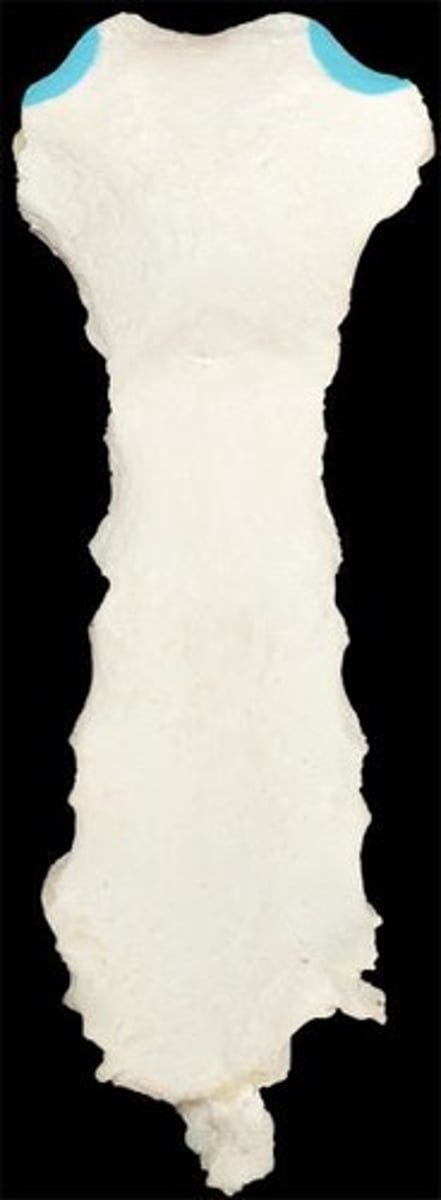

sternum

What is this bone?

manubrium

What is this structure?

body of sternum

What is this structure?

sternal angle

What is this structure?

clavicular notch